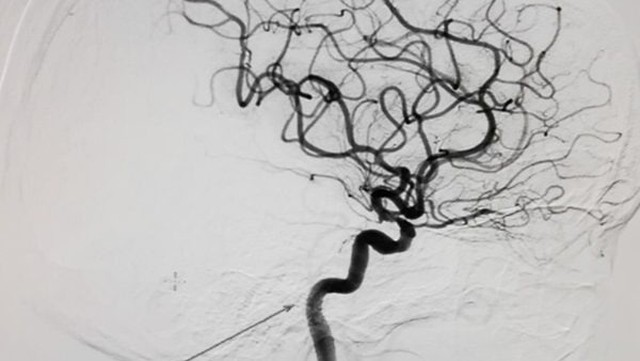

Kỹ thuật DSA là một công cụ quan trọng hỗ trợ trong việc chẩn đoán và theo dõi các bệnh lý liên quan đến mạch máu, đặc biệt trong các ca phẫu thuật can thiệp đòi hỏi hiểu biết sâu sắc về cấu trúc và tình trạng của các mạch máu.

Phình động mạch não là một loại bệnh thường gặp nguy hiểm, có tỷ lệ tử vong cao khi bị vỡ. Phình động mạch não thường gây đau đầu, mất thị lực, cứng cổ, tê/ yếu một bên mặt, buồn nôn và nôn. Bệnh có thể phát hiện sớm ở nhóm người có yếu tố nguy cơ cao bằng chẩn đoán hình ảnh như CT 64 lát cắt, MRI và DSA. Điều trị bằng cách đặt stent, coil hay phẫu thuật mở để đặt kẹp mạch máu.